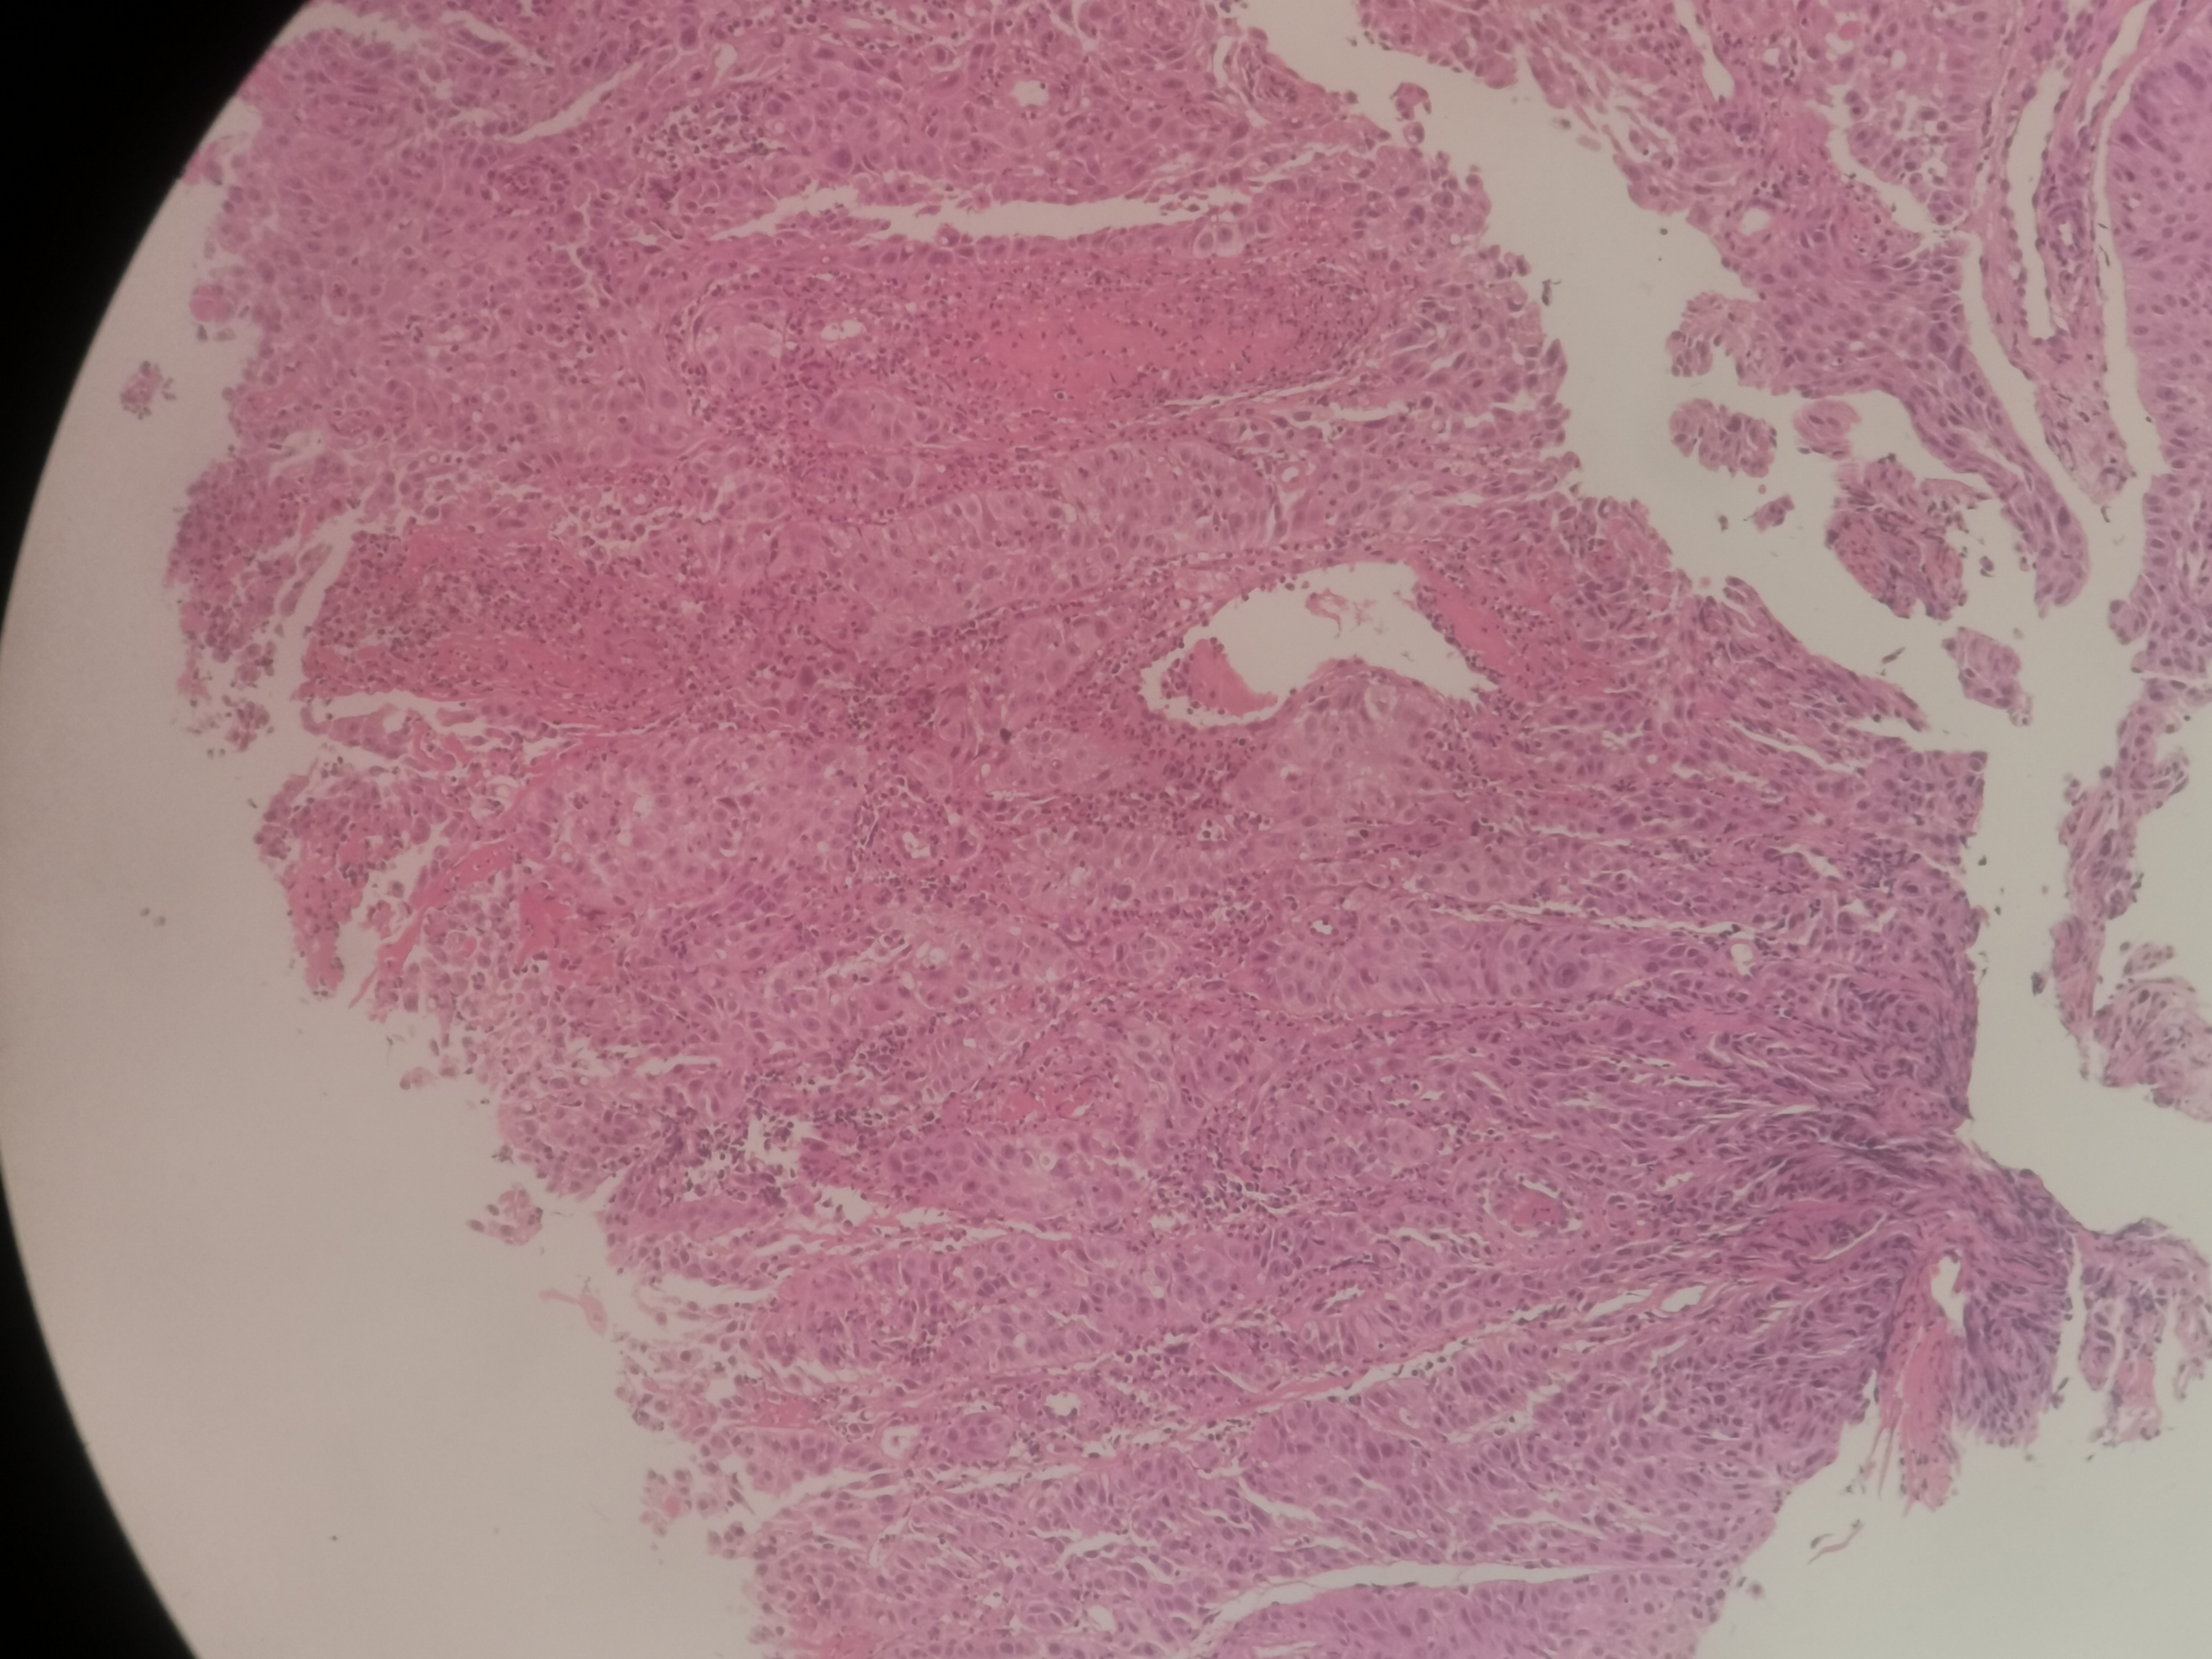

求助,请老师鳞状细胞癌高分化吗?

性别

男

年龄

55岁

临床诊断

食道肿物?

一般病史

食道35~40厘米处不规则增生性肿物,环管腔1/2表面充血、糜烂,质脆,易出血

标本名称

食道活检

大体所见

送检组织0.15x0.1x0.1厘米~0.45x0.3x0.3厘米5块

高分化鳞状细胞癌